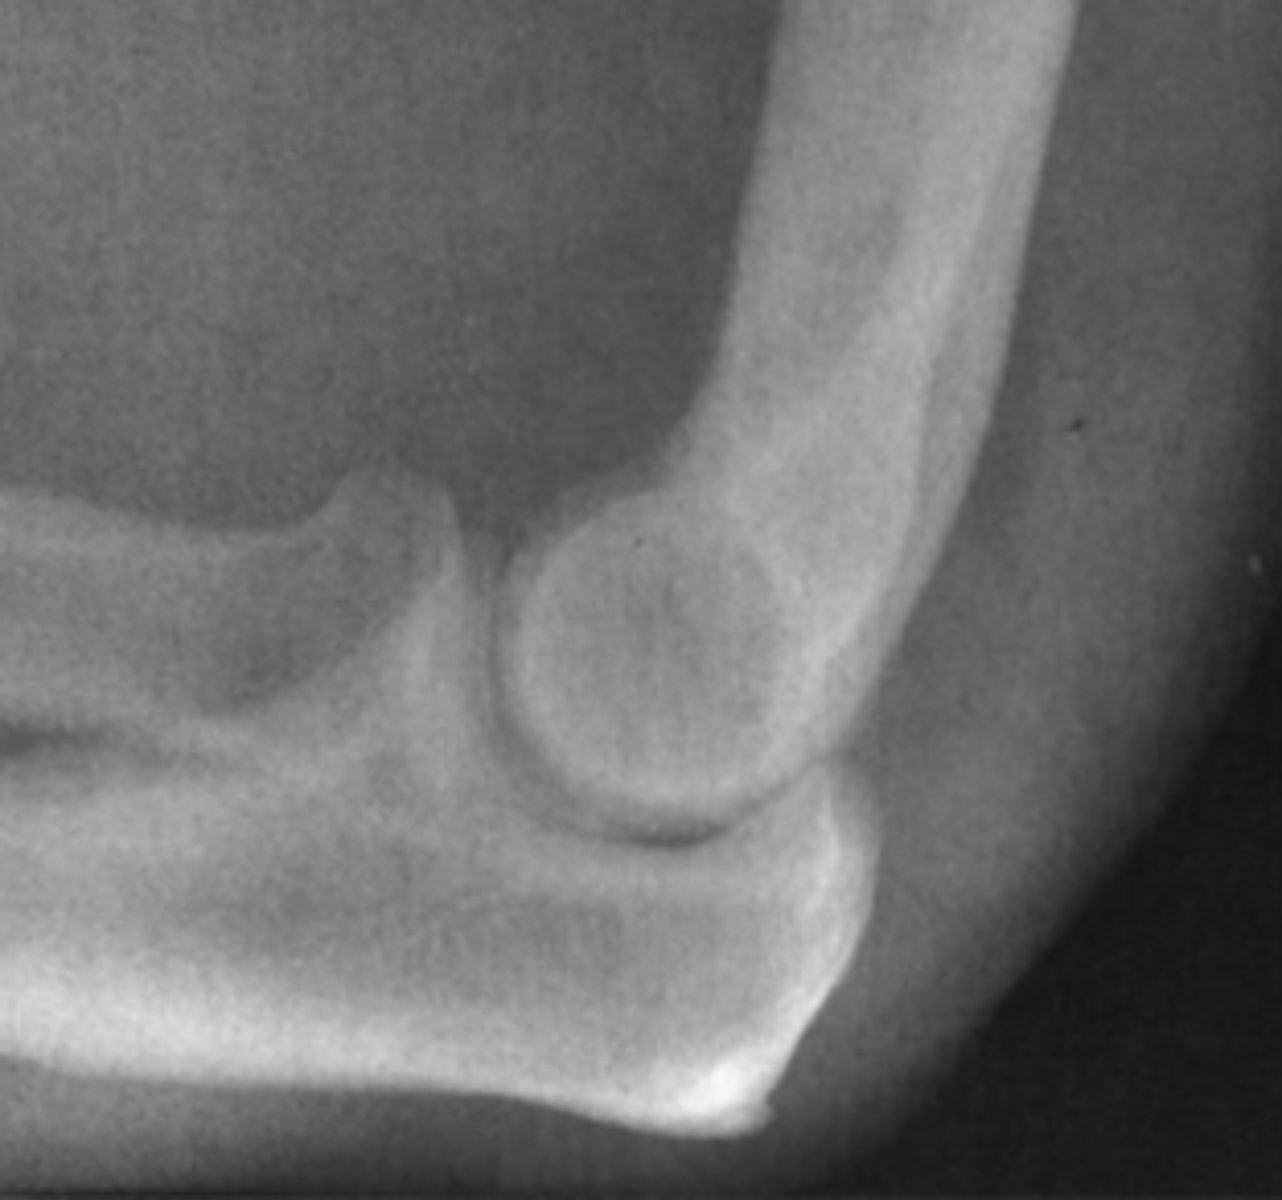

While moonlighting in the emergency department of a small community hospital, you examine a 25-year-old man who fell on an outstretched

hand and now complains of elbow pain. You obtain an AP and lateral view of his elbow (lateral view of the elbow).

You first examine the lateral view of the elbow in Case

6-3 (Figure 6-10). You find

A. a lytic lesion in the distal humerus.

B. displacement of the fat pads of the elbow.

C. a fracture through the proximal ulna.

D. dislocation of the elbow.

Answer

B.

You have the anterior sail sign and posterior fat pad sign.